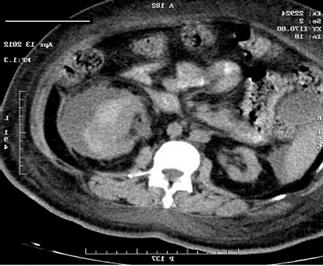

♦ Microangiopatía trombótica

♦ Estenosis de la arteria renal

♦ Nefritis tubulointersticial crónica

♦ Infecciones del tracto urinario / pielonefritis